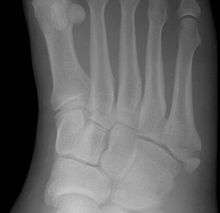

This injury should be differentiated from the developmental apophysis (5th metatarsal tuberosity) commonly and normally occurring at this site in adolescents. Differentiation is possible by characteristics such as absence of sclerosis of the fractured edges (in acute cases) and orientation of the lucent line: transverse (at 90 degrees) to the metatarsal axis for the fracture (due to avulsion pull by the peroneus brevis muscle inserting at the proximal tip) - and parallel to the metatarsal axis in the case of the apophysis. Diagnostic x-rays include anteroposterior, oblique, and lateral views and should be made with the foot in full flexion.

A legitimate concern in any fracture is whether the fracture will heal quickly and without complication. Failure of the fractured ends to unite is called non-union and its frequency varies with the fracture site, some fracture sites being notorious for non-union. An example of such would be a scaphoid (navicular) fracture of the wrist. Such a complication also involves fractures of the proximal end of the fifth metatarsal, such as the Jones fracture. This has been the subject of interest, and initially led to the description of three zones at the proximal end of the fifth metatarsal.

Zones I and II have been associated with relatively guaranteed union and this union has taken place with only limited restriction of activity combined with early immobilization. On the other hand, zone III has been associated with either delayed or non-union and, consequently, it has been generally agreed that fractures in this area should be considered for some form of internal immobilization, such as internal screw fixation. More recently, because of the similar behavior of the original zones I and II, it has been suggested that zones I and II be combined leading to current recommendations for two zones, zone I being associated with uncomplicated union, and zone II being prone to nonunion and therefore considered for internal fixation.

These zones can be identified anatomically and on x-ray adding to the clinical usefulness of this classification.[3] It should be emphasized that surgical intervention is not, by itself, a guarantee of cure and has its own complication rate. Other reviews of the literature have concluded that conservative, non-operative, treatment is an acceptable option for the non-athlete.[4]